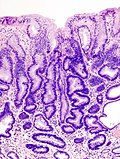

Stomach adenoma

Stomach adenoma, also gastric adenoma, is a precursor to adenocarcinoma of the stomach.

Microscopic

- Histologic criteria similar to columnar dysplasia in the esophagus.

- The threshold is much lower than in the colon and rectum.